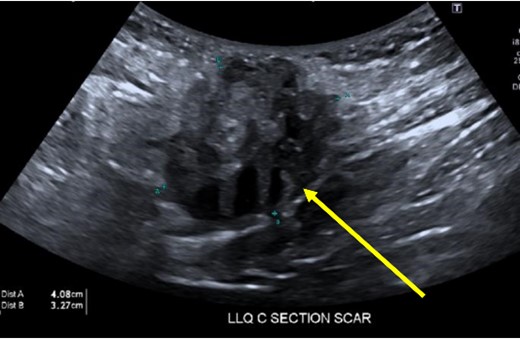

A 33-year-old female with past medical history of uterine fibroids and cervical insufficiency was initially seen with peri-incisional pain at the site of her Pfannenstiel scar since an emergency Cesarean section 16 months prior for eclampsia. She reported cyclical pain since that time, worse during menstruation and associated with swelling that resolved after menstruation. The discomfort and swelling persisted for 1 week after her last menstrual period, which prompted her to present for evaluation. On examination, a palpable, exquisitely tender mass was appreciated over the right side of her Pfannenstiel incision without evidence of discharge, erythema, or ulceration. Laboratory workup proved normal, and CT imaging revealed a soft tissue abscess-like collection anterior to the rectus abdominis muscle in the lower abdomen measuring 2.2 cm without intra-abdominal involvement (Fig. 9a and b). We deemed her a candidate for operative intervention given a high suspicion for endometrioma and her symptomatology.

Computed tomography axial (a) and sagittal (b) views of a 2.2 × 2.0 cm enhancing mass on the abdominal wall (arrows).